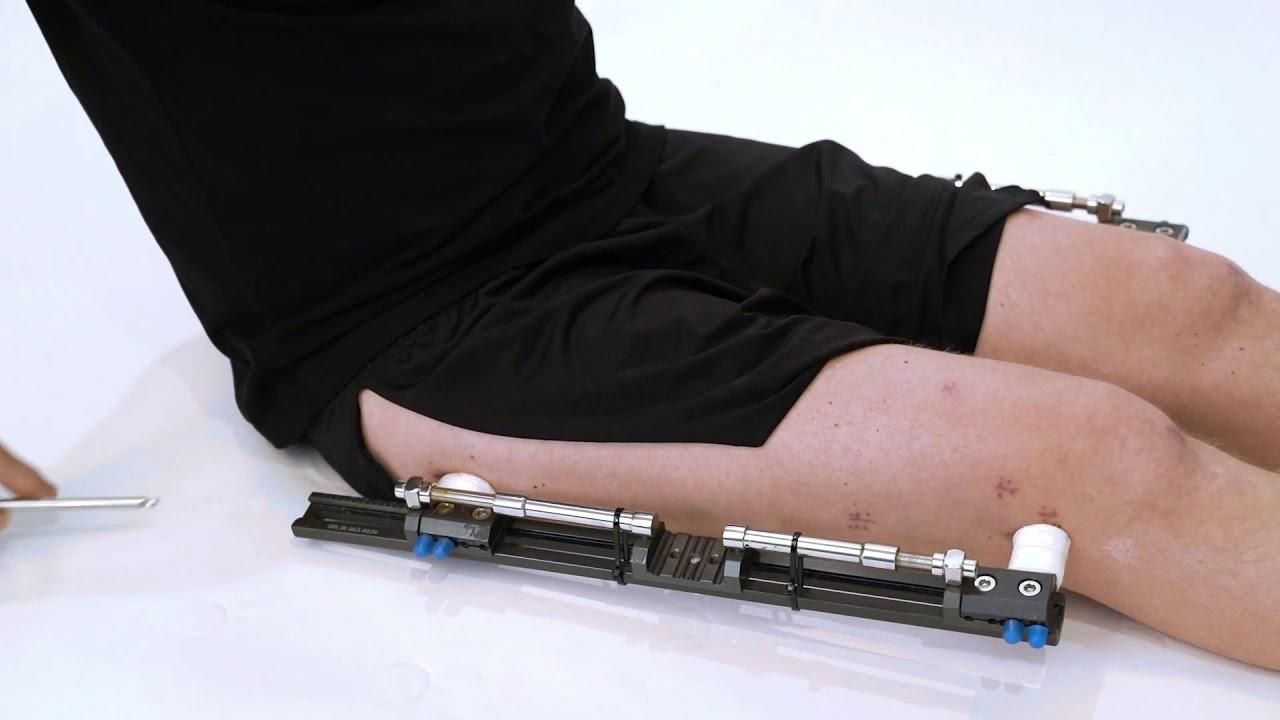

Fitbone Yöntemi

Fitbone® Yöntemi ile Boy Uzatma Tamamen İçten (Internal) Motorize Uzuv Uzatma Teknolojisi